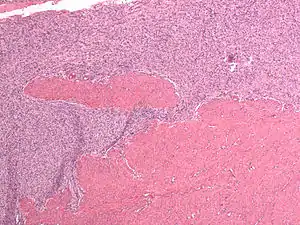

Endometrial Stromal Sarcoma, High-Grade

Undifferentiated uterine sarcoma, or undifferentiated (high-grade) endometrial stromal sarcoma, does not resemble normal endometrial stroma and behaves much more aggressively, frequently metastasizing. The differential includes leukemia, lymphoma, high-grade carcinoma, carcinosarcoma, and differentiated pure sarcomas.